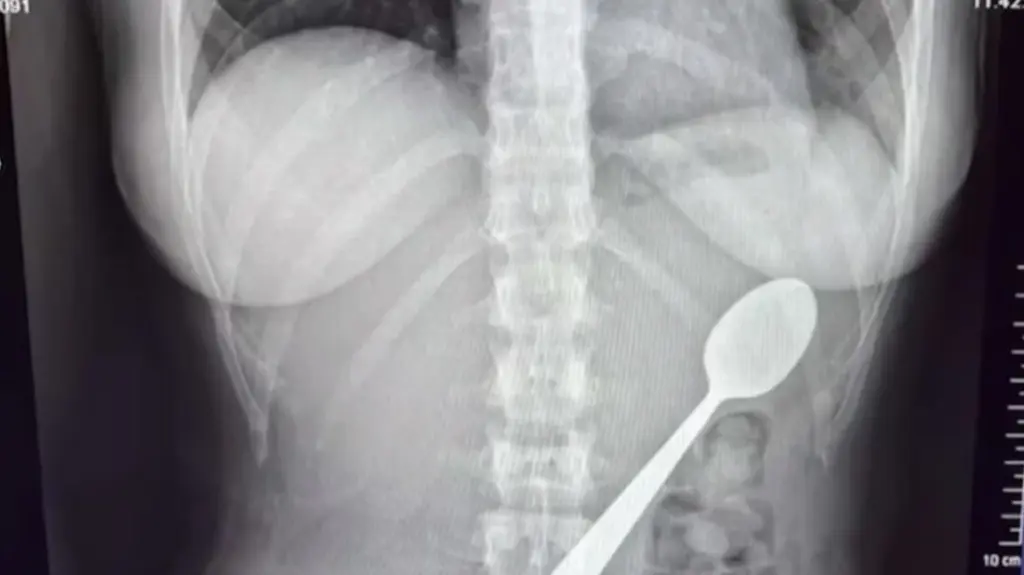

28χρονη στο Βέλγιο κατάπιε κουτάλι 17 εκατοστών όταν ο σκύλος της πήδηξε πάνω της [βίντεο]

Το αντικείμενο αφαιρέθηκε με γαστροσκόπηση δύο ημέρες μετά· η ασθενής αρχικά δεν είχε αποκαλύψει το περιστατικό στον σύντροφό της.

Το αντικείμενο αφαιρέθηκε με γαστροσκόπηση δύο ημέρες μετά· η ασθενής αρχικά δεν είχε αποκαλύψει το περιστατικό στον σύντροφό της.